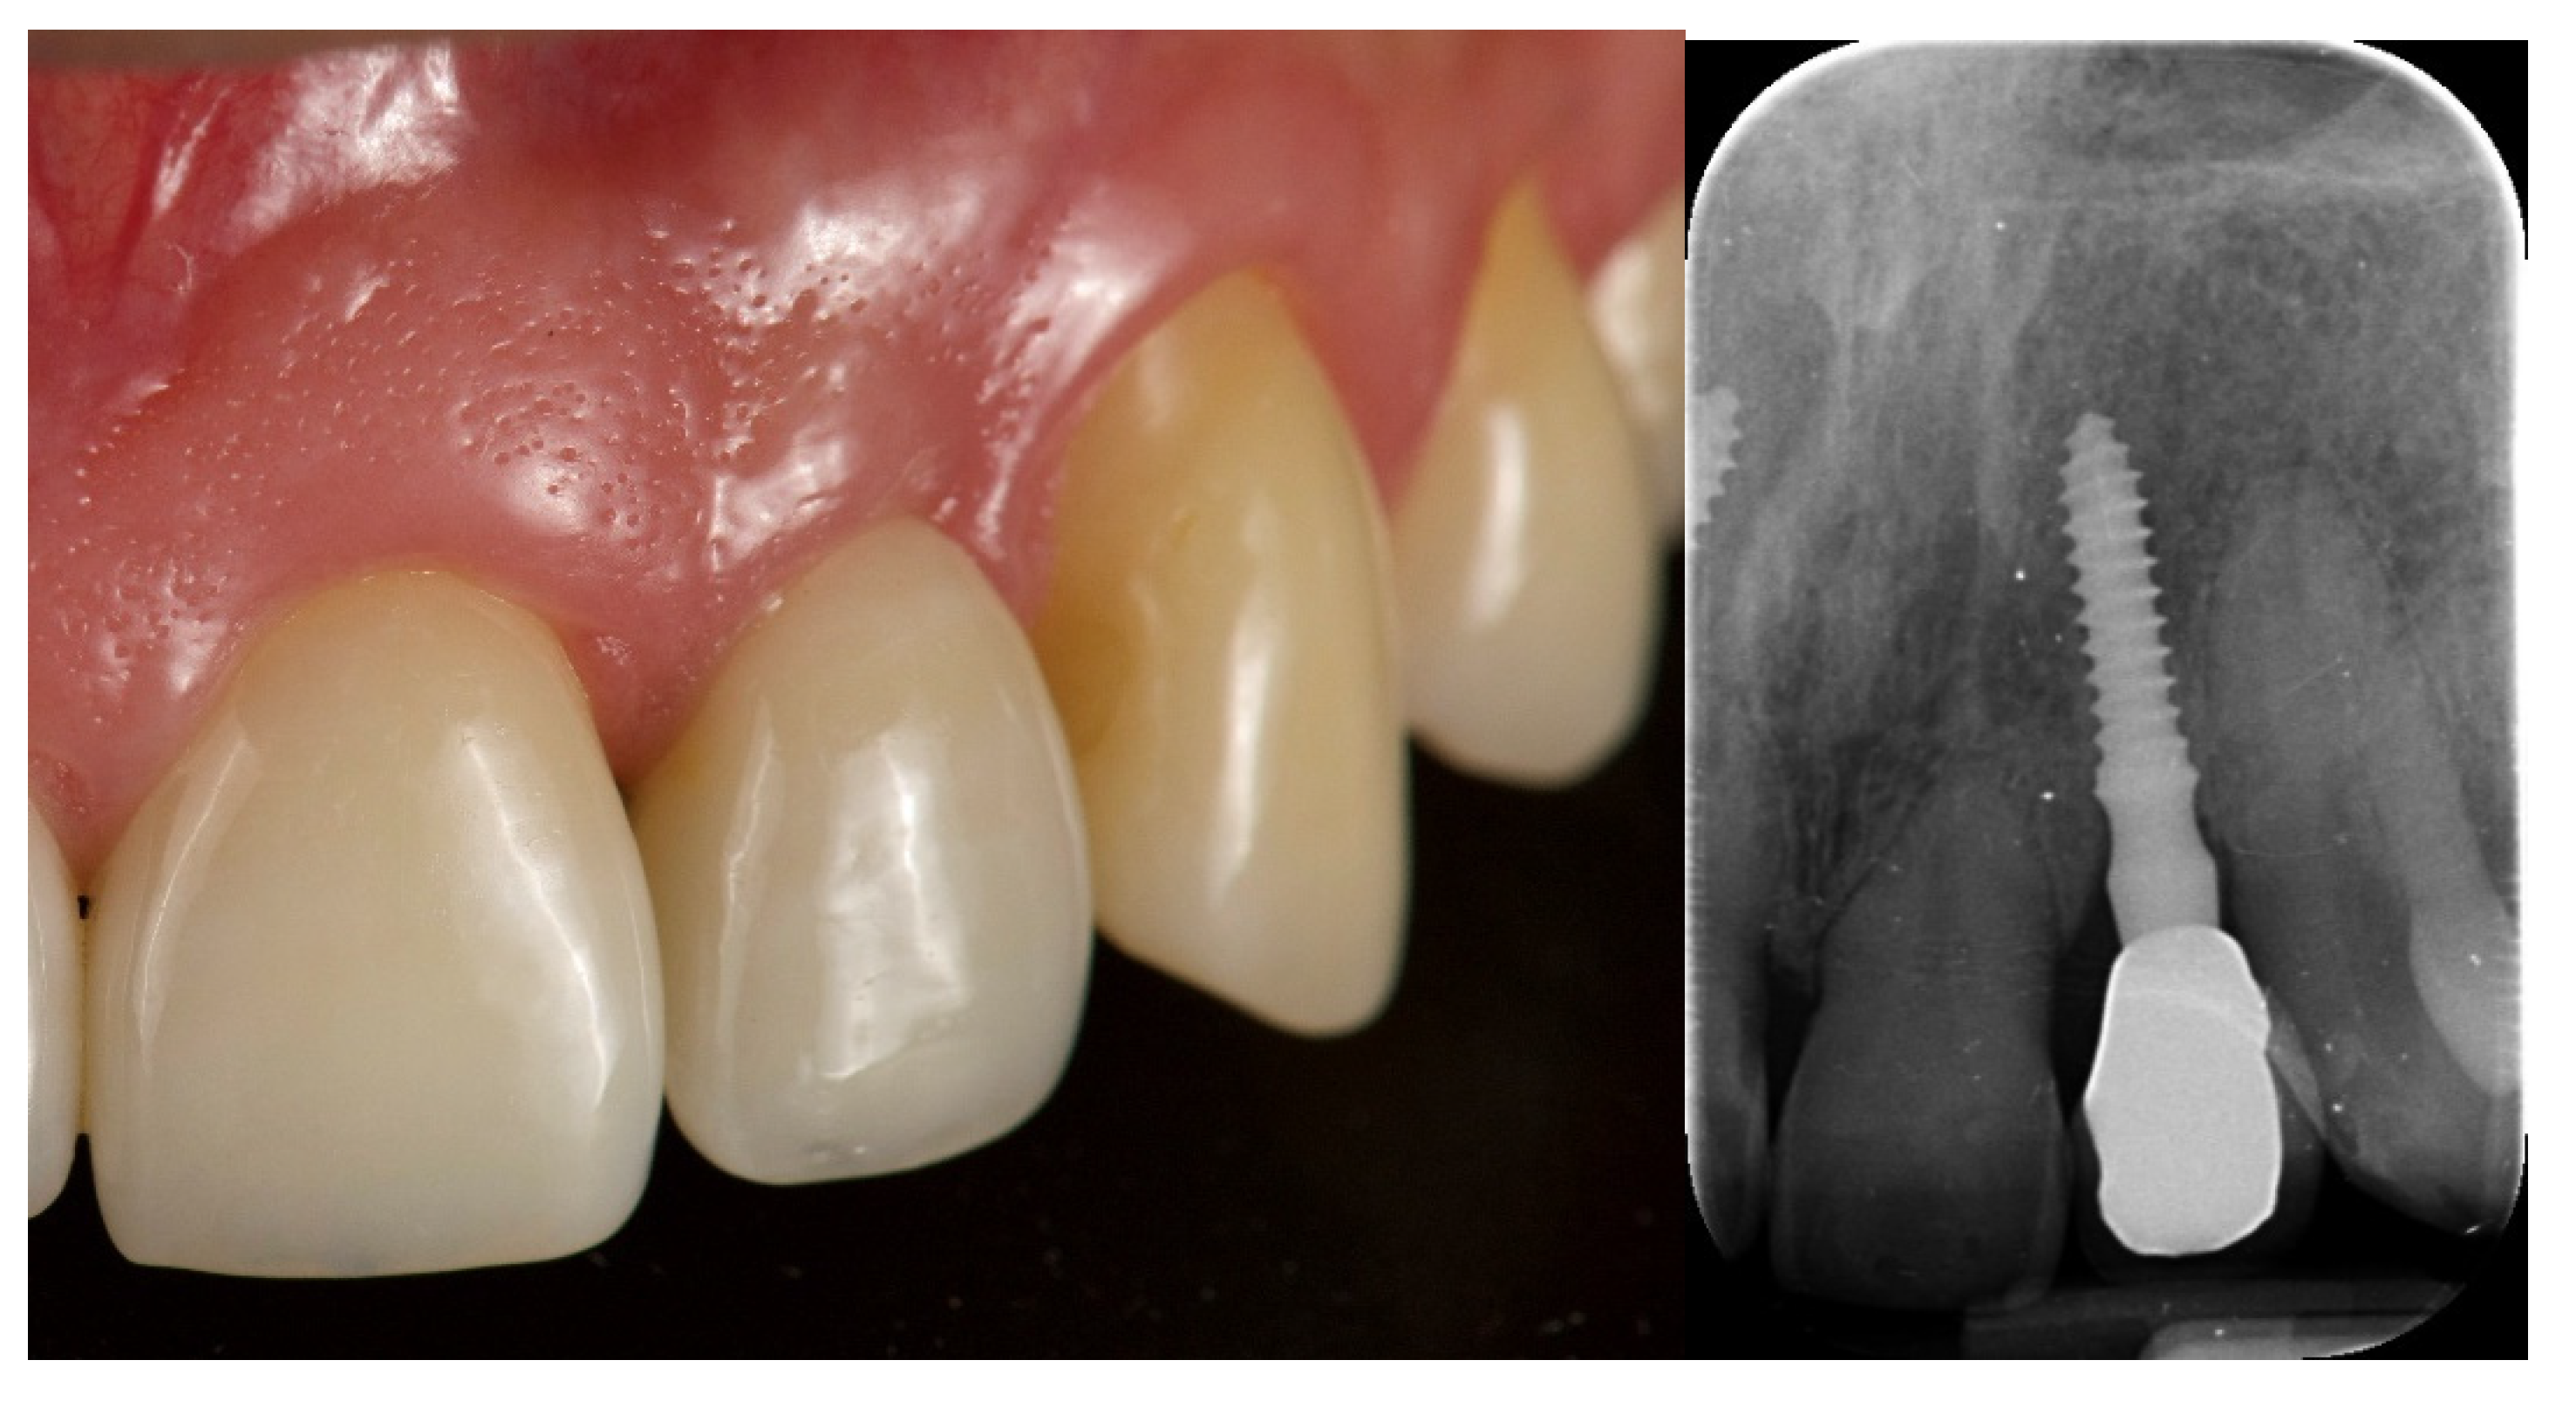

- Esthetic evaluation of clinical pictures, including at least two adjacent teeth, taken at two years after loading was done following the pink esthetic score (PES) proposed by Fürhauser et al., in 2005 [31]. In brief, the PES score evaluates seven variables: mesial papilla, distal papilla, soft tissue level, soft tissue contour, alveolar process deficiencies, soft tissue color and texture. A 0-1-2 scoring system was used, with a maximum achievable score of 14 per site.

| PES 3 at the 2-year follow-up | 12.6 ± 0.97 | 12.2 ± 0.92 | 0.3554 |